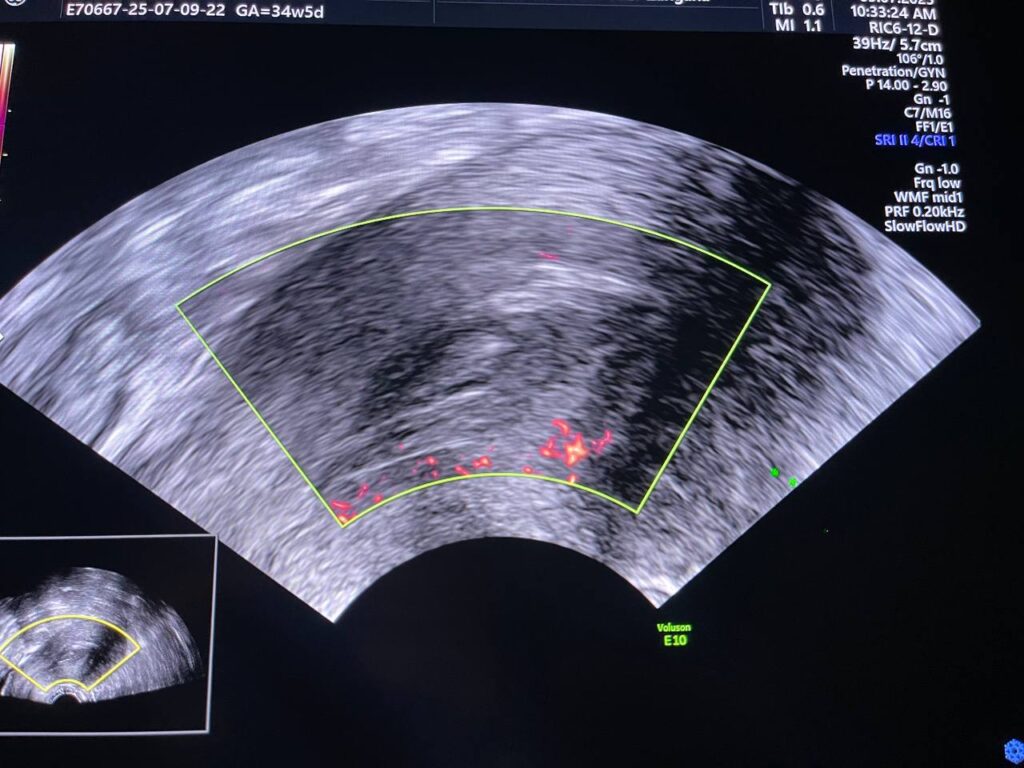

Bulky size, A/V uterus,  endometrial lining thickness 22mm, the cavity occupied by heterogenous avascular lesion 42x16mm , mostly blood clots? in addition to presence of few cysts with instinct  left anterior upper part of the endo myometrial junctional zone , in area size about 11.5x9mm, mostly remains of hydatiform wall  , please for further study   , no fibroid

This patient has high BHCG level , with History of H Mole on march 2025